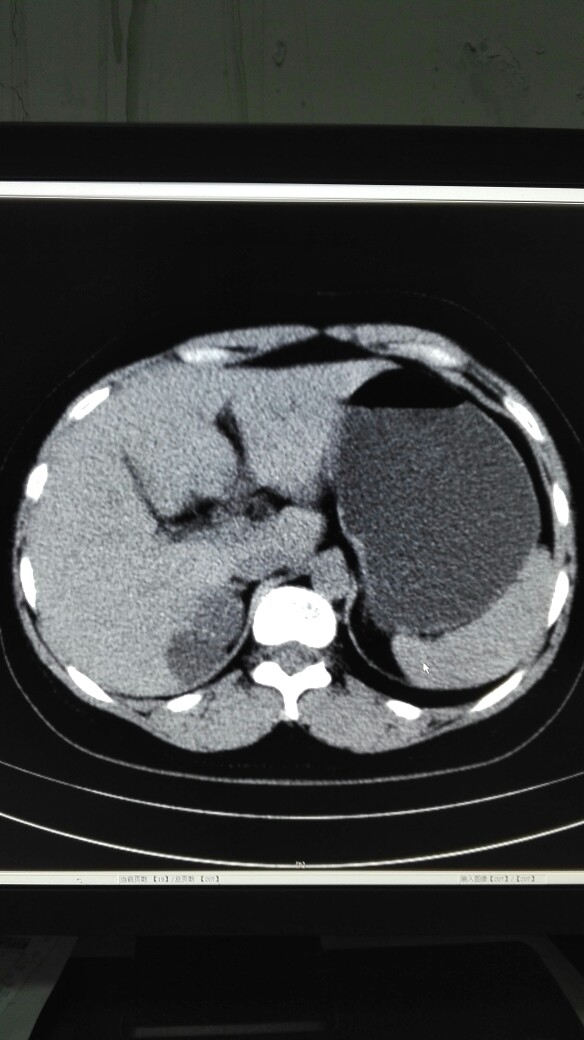

患者女,40岁,医院职工家属。B超体检时发现肝肾间多发囊性占位性病变。行腹部平扫示:右肾上腺区囊性占位,有分割和钙化点,右肾受压下移。诊断意见:右肾上腺囊腺瘤可能性大,建议进一步检查明确。后到市级医院检查并切除手术,病理切片考虑肾上腺囊肿。今腰部不适复查CT片。